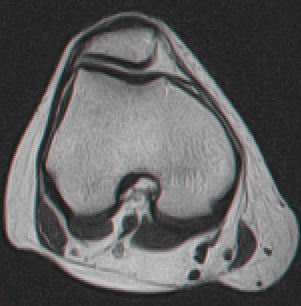

Fig. 1.11 Imagine RMN, sectiune sagitala la nivelul compartimentului intern al genunchiului drept, genunhi in extensie |

|

Fig. 1.12 Imagine RMN, sectiune transversala la nivelul articulatiei femuropatelare a genunchiului drept, genunchi in extensie |